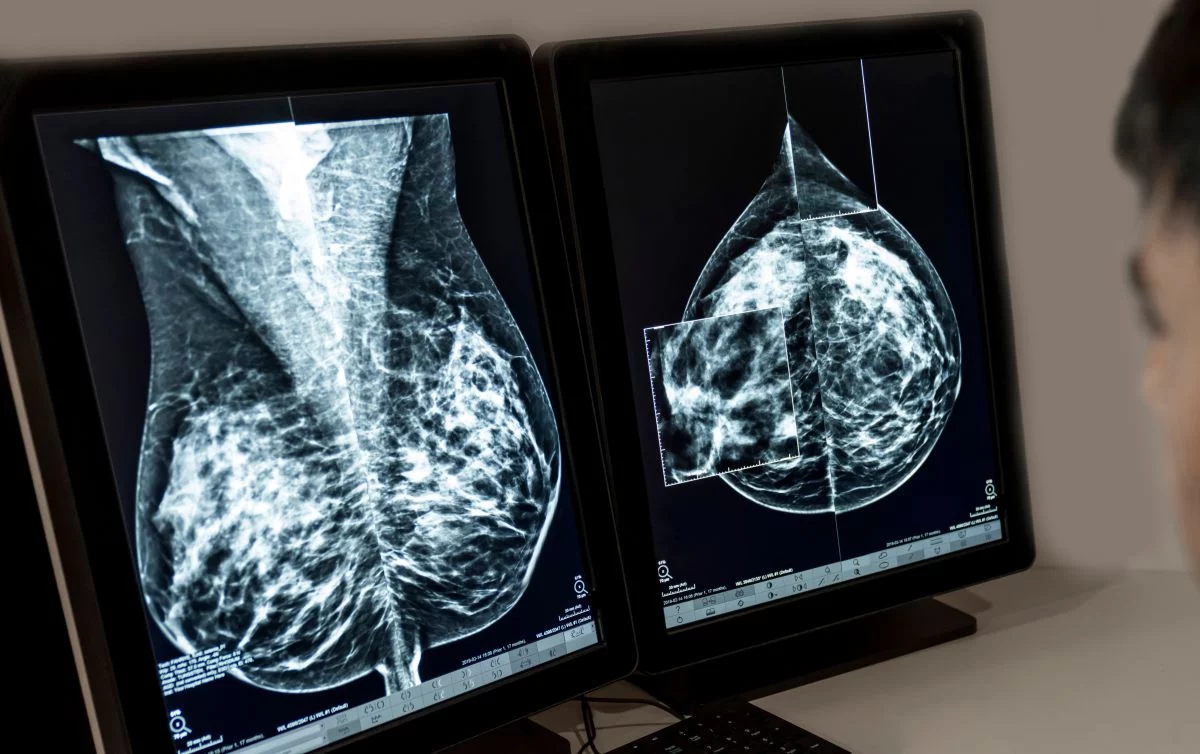

El cáncer de mama es el cáncer que se diagnostica con mayor frecuencia en Europa, y aproximadamente el 70% de los casos, en etapas tempranas de la enfermedad. A pesar de las opciones terapéuticas actuales, las personas diagnosticadas con cáncer de mama localizado HR+/HER2- en estadios II y III siguen corriendo el riesgo de que su cáncer reaparezca a largo plazo, a menudo como una enfermedad avanzada incurable.